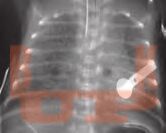

Сурфактант в неонатологии. Профилактика и лечение респираторного дистресс-синдрома новорожденных

Фундаментальное и практическое руководство по профилактике и лечению РДС. Детальный разбор всех препаратов, методов респираторной поддержки и их интеграции в комплексную терапию на основе доказательной медицины. Для неонатологов, акушеров, педиатров и реаниматологов

В книге представлен систематический обзор современных представлений о системе сурфактанта, позволяющий читателю понять связь между состоянием этой системы, биофизическими процессами в альвеолах новорожденного, физиологическими особенностями дыхания, патофизиологическими механизмами дыхательных нарушений и принципами их коррекции.

Приведена информация о биохимии, физиологии и фармакологии сурфактанта, детально характеризуются все препараты сурфактанта, применяющиеся в клинической практике.

Особое внимание уделено клиническим аспектам диагностики, профилактики и лечения респираторного дистресс-синдрома у недоношенных новорожденных с позиций доказательной медицины. Детально изложены вопросы практического применения препаратов сурфактанта в различных клинических ситуациях, причем применение сурфактанта рассматривается не как изолированный метод лечения, а как составная часть комплексного подхода. Подробно описаны различные методы инвазивной и неинвазивной респираторной поддержки, приведено патофизиологическое обоснование их дифференцированного применения.